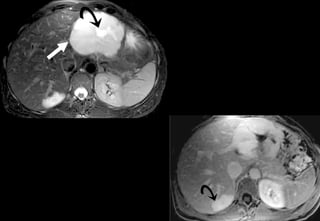

CHC và tưới máu ko đồng đều

CHC thâm nhiễm với rò động mạch- cửa

CHC nhỏ

< 2 cm đường kính

Vỏ

Tín hiệu thay

đổi

tăng T2

CHC nhỏ < 2 cm

Tăng sinh mạch đồng nhất và lan tỏa

• + WASHOUT thì cửa

• Đơn độc : 15% CHC nhỏ

Chẩn đoán phân biệt 2 à 8%

u mạch, shunts động tĩnh mạch, HNF...